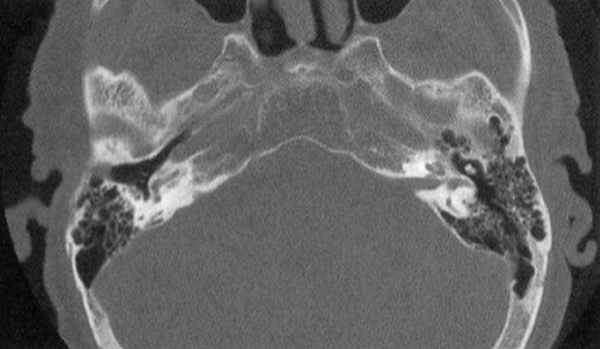

МСКТ височной кости — КТ-картина образования пирамиды правой височной кости с костно-деструктивными изменениями, правостороннего среднего отита. Образование на МСКТ височной кости отграничено сверху базальным завитком улитки и преддверием, снизу — яремной веной, медиально — твердой мозговой оболочкой задней черепной ямки, латерально — гипо- и мезотимпанумом, спереди — вертикальной частью внутренней сонной артерии, сзади — сагиттальным ПК, внутренним слуховым проходом (рис. 1). Рис. 1. МСКТ височной кости (правое ухо). КТ-картина инфралабиринтной холестеатомы пирамиды височной кости (а — аксиальная проекция, б — коронарная проекция).

С учетом данных тональной аудиометрии (выраженное нарушение слуховой функции у пациентки) и МСКТ височной кости была поставлена цель — максимальная элиминация холестеатомы с сохранением функции Л.Н. Реконструктивный слухоулучшающий этап операции, несмотря на костно-воздушный интервал в 50 ДБ, не рассматривался из-за костной деструкции холестеатомой переднего и заднего отделов лабиринта.

По данным МСКТ височной кости, у пациентки отсутствовали признаки выраженного предлежания СС и высокого расположения луковицы яремной вены, поэтому в качестве хирургического подхода к инфралабиринтной холестеатоме пирамиды височной кости был выбран трансмастоидальный-инфралабиринтный доступ с удалением пораженной холестеатомой улитки.